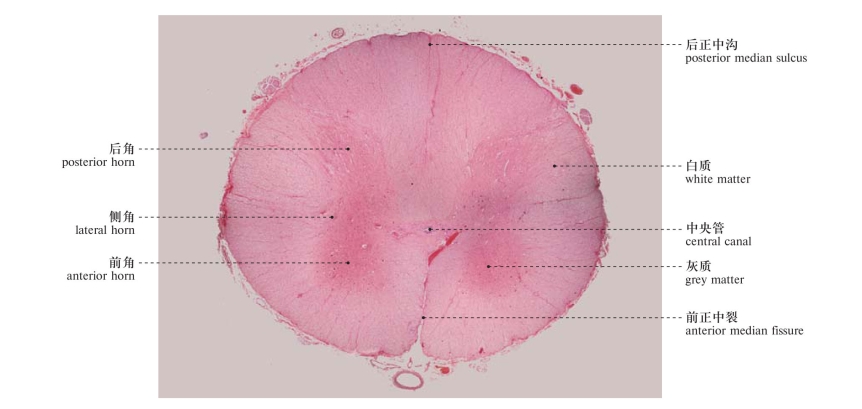

图513 脊髓(人脊髓,横切面,×40)

Spinal cord (human spinal cord, transverse section, ×40)